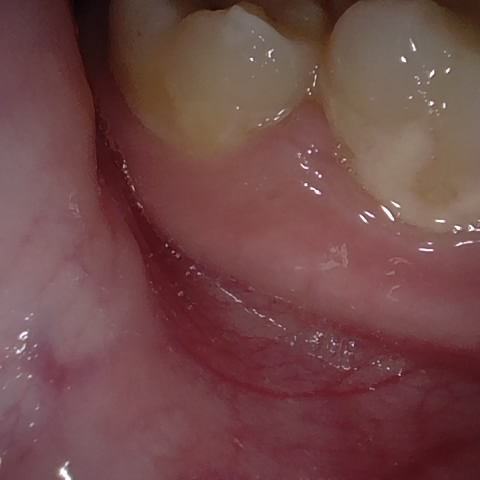

Annotated as "Bad"